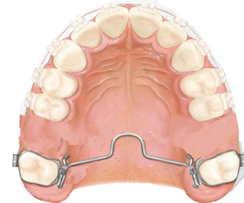

Camuflaje con exodoncia de molares permanentes

Esta técnica consiste en la exodoncia de primeros molares permanentes superiores con la colocación de aparatología fija con Brackets de baja fricción, alambres redondos y delgados, un anclaje moderado mediante una barra transpalatina a nivel de los segundos molares permanentes (figura 8), permitiendo el menor movimiento posible del sector posterior evitando la pérdida de anclaje, se realiza por tres fases posteriores: corrección de la Clase II, cierre de espacios y asentamiento, el tiempo promedio del tratamiento es de dos años y medio 1.

Figura 8. Exodoncia de primeros molares superiores.

Elaboración: Los autores.